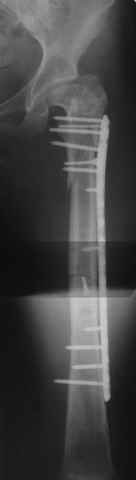

Re: Перелом проксимального отдела диспластичного б

Прошу прощения, со снимками глюк произошел. Высылаю. С уважением Евгений У.